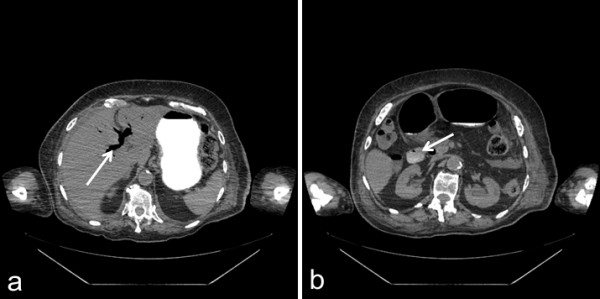

Figure 2.

Computed tomography image (axial view) showing Rigler’s triad. a Gastric distension and pneumobilia (arrow). b Gallstone in the duodenal bulb (arrow).